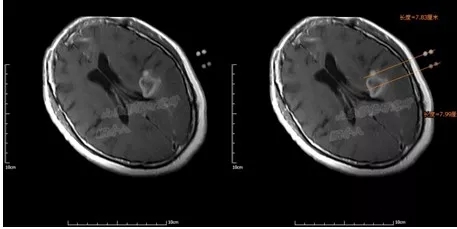

术后24小时内MRI/CT图像融合

MR/CT融合图像解决了I125放射性粒子在磁共振图像上显示不清、CT图像病灶轮廓勾画

困难的缺点,达到精准的病灶与粒子的空间分布显示,有利于术后的TPS验证。